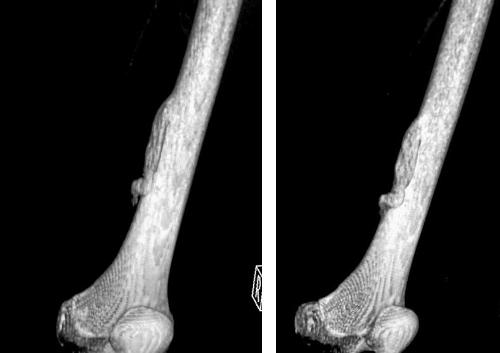

Наиболее распространенным заболеванием является остеоид-остеома большеберцовой кости. Эта опухоль долгое время может не проявлять себя, и многие пациенты даже не подозревают о её наличии. Остеоид-остеома бедренной кости встречается реже и также редко вызывает симптомы.

Диагностика включает целенаправленную рентгенографию, которая позволяет оценить структуру тканей вокруг образования (плотное или губчатое вещество в зависимости от места возникновения опухоли). Четкие изображения помогают детально рассмотреть остеому, её форму и размеры.

Также могут быть назначены магнитно-резонансная томография и компьютерная томография. МРТ предоставляет более детальную информацию о новообразованиях. На снимках можно увидеть расположение опухоли и исключить болезнь Гарднера.

Локализируется опухоль в различных костях скелета, но чаще в бедренной и большеберцовой костях, а также в структурах позвонков. Основное клиническое проявление остеоид-остеомы — боль, носящая изнуряющий характер, усиливающаяся в ночное время. Боль определяется в очаге поражения, редко иррадиирует.